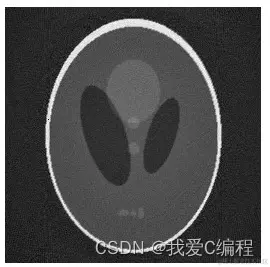

2.仿真效果预览

matlab2013B仿真结果如下:

2.png

3.png

4.png

5.png

6.png

7.png